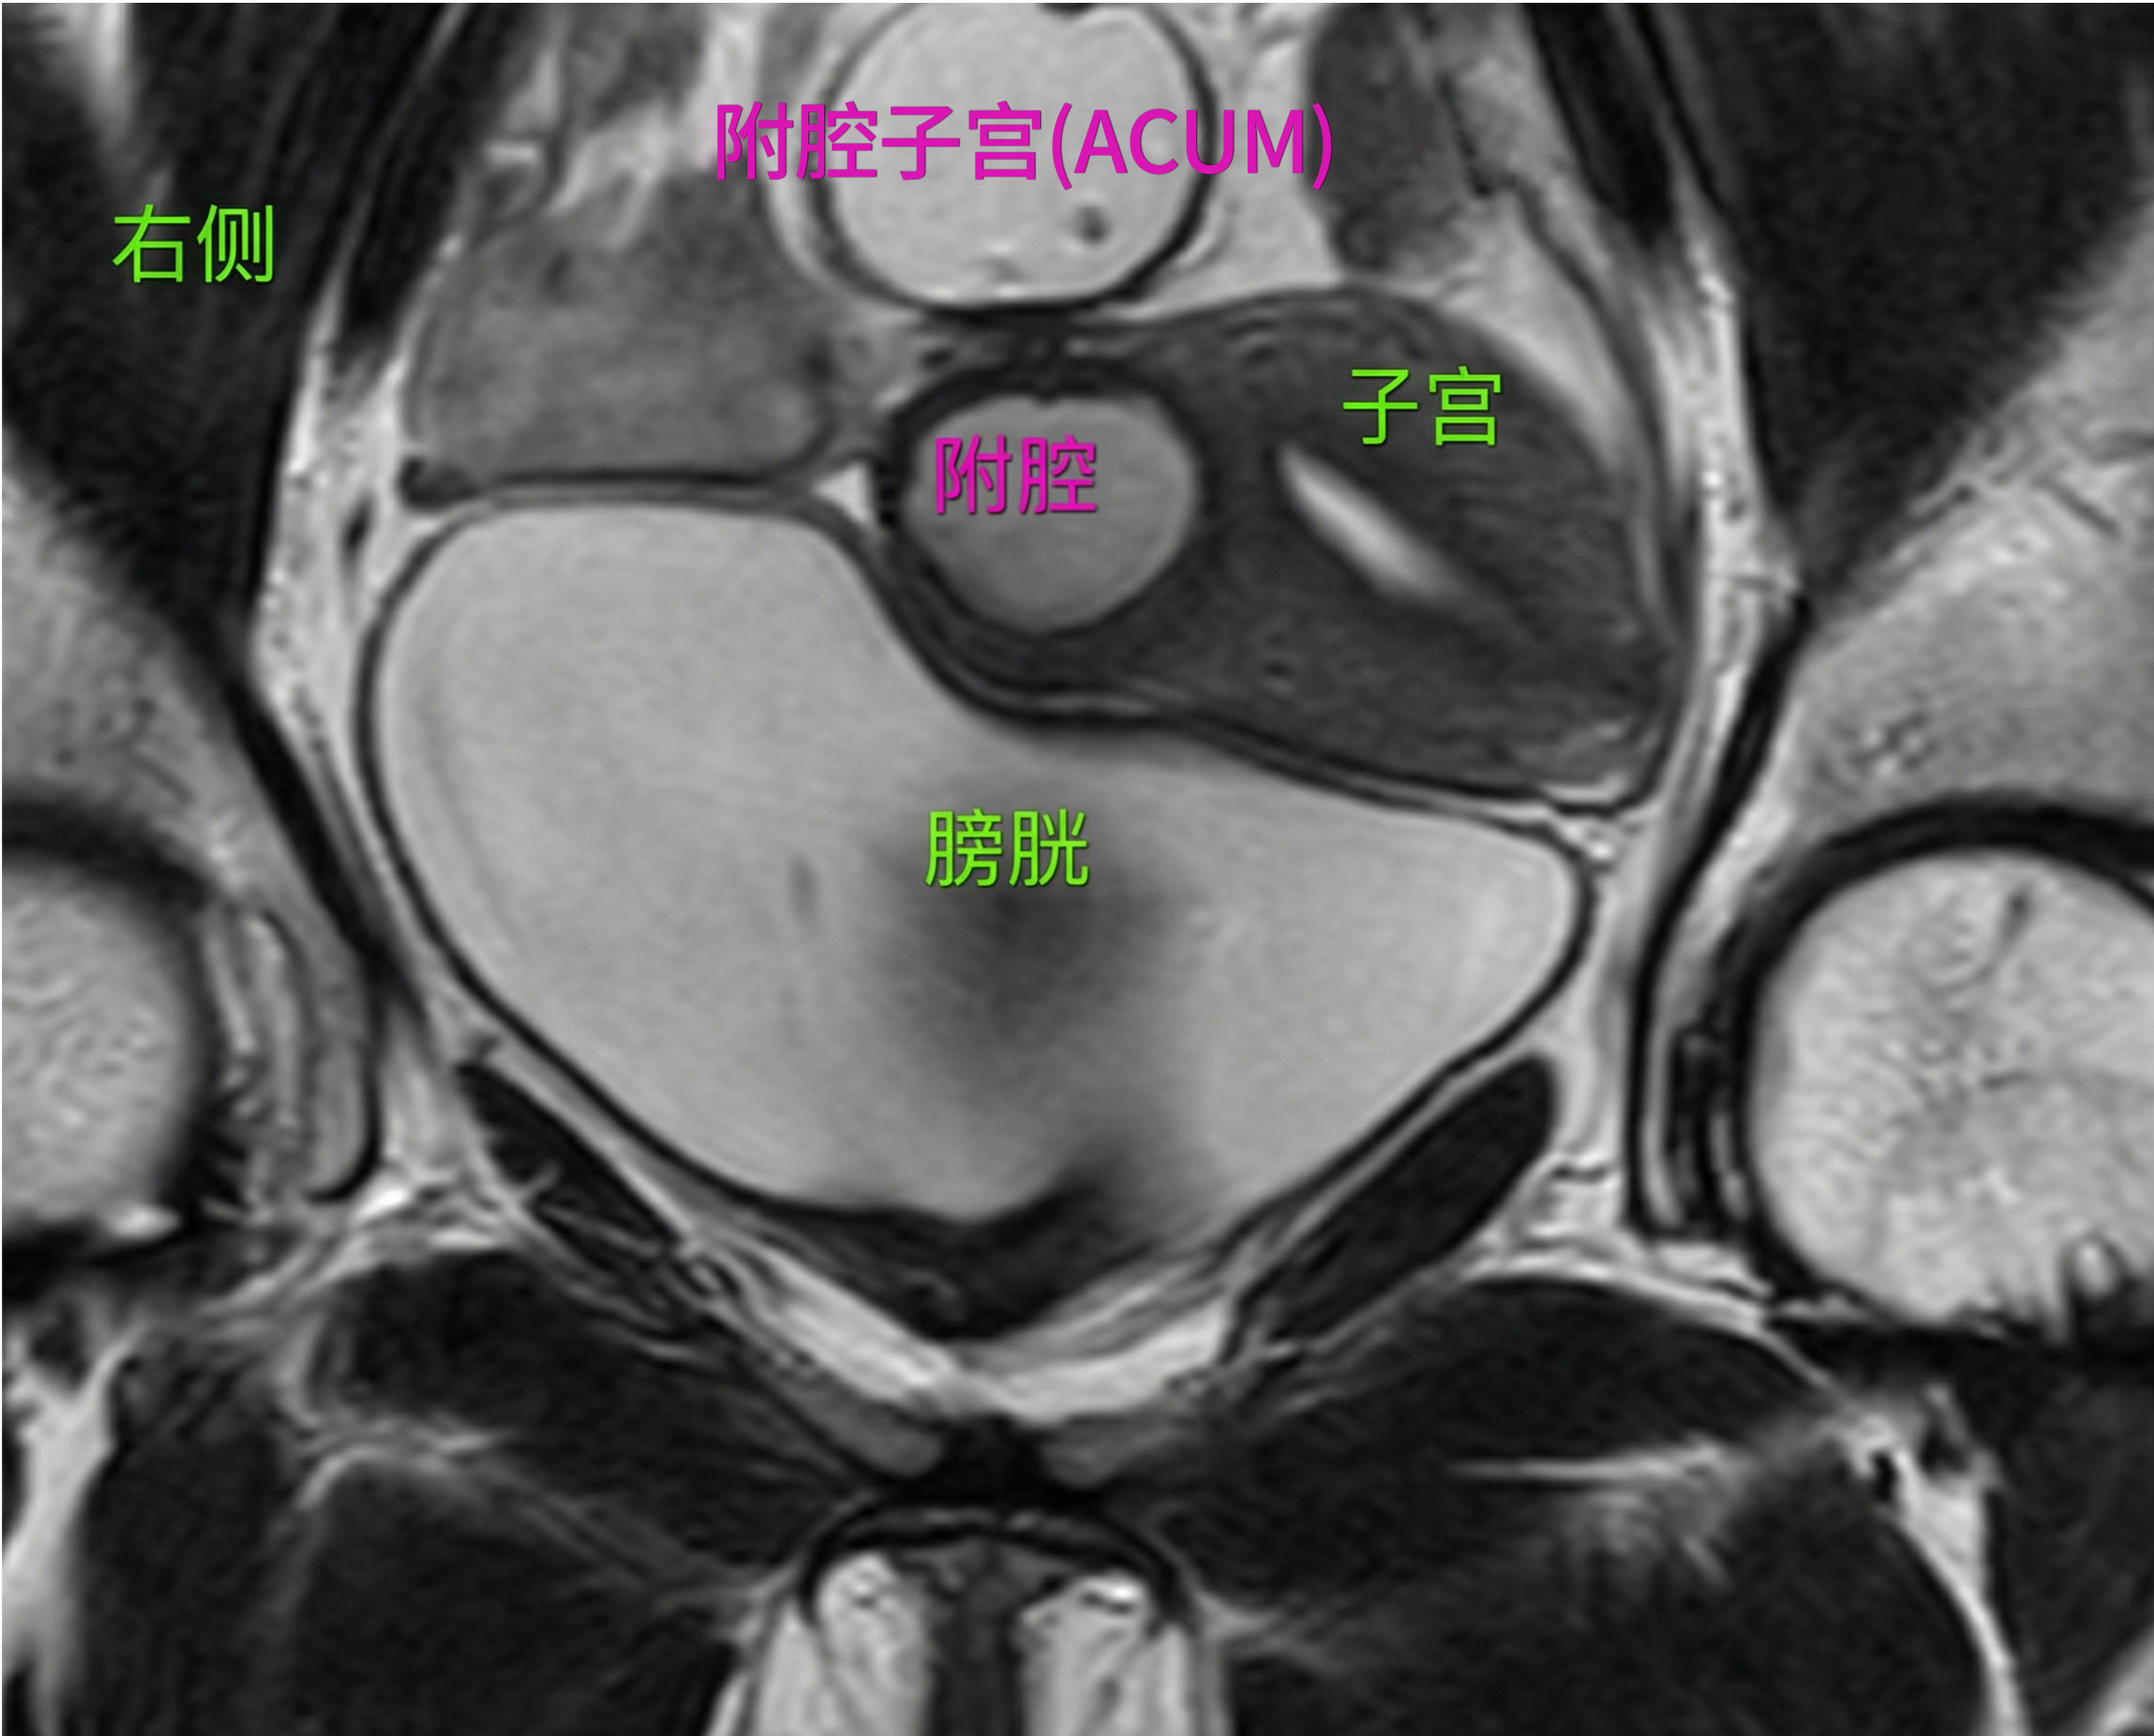

附腔子宫(ACUM)是一种先天性的苗勒管发育异常,但它并非极其罕见,只是长期以来未能被充分认识。其典型特征是在子宫肌层内形成一个孤立的、不与主宫腔相通的副腔,而这个副腔内壁覆盖着具有功能的子宫内膜组织。

诊断ACUM的最大挑战在于其“伪装性”。它常常隐藏在看似“正常”的子宫之中。因此,精准的影像学评估至关重要。虽然术前的MRI或三维超声可以提供重要线索,但根据原始案例的经验,术中超声(Intraoperative Sonography)扮演了“终极侦探”的角色。它能够在手术过程中实时、动态地探查子宫肌层,精确地定位病灶的位置、大小和数量,甚至发现一些术前影像未能识别的、对称分布的微小病灶,从而为彻底清除病灶、避免复发提供了决定性的指引。